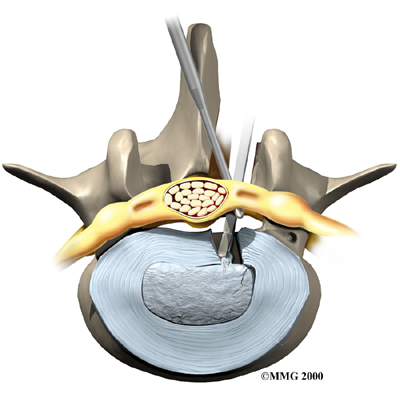

Microdiscectomy

Microdiscectomy is becoming the standard surgery for lumbar disc herniation. The procedure is used when a herniated disc is putting pressure on a nerve root. It involves carefully taking out part of the problem disc (discectomy). By performing the operation with a surgical microscope, the surgeon only needs to make a very small incision in the low back. Categorized as minimally invasive surgery, this surgery is thought to be less taxing on patients. Advocates also believe that this type of surgery is easier to perform, that it prevents scarring around the nerves and joints, and that it helps patients recover more quickly.

Related Document: FYZICAL Sun City Las Vegas Guide to Lumbar Discectomy